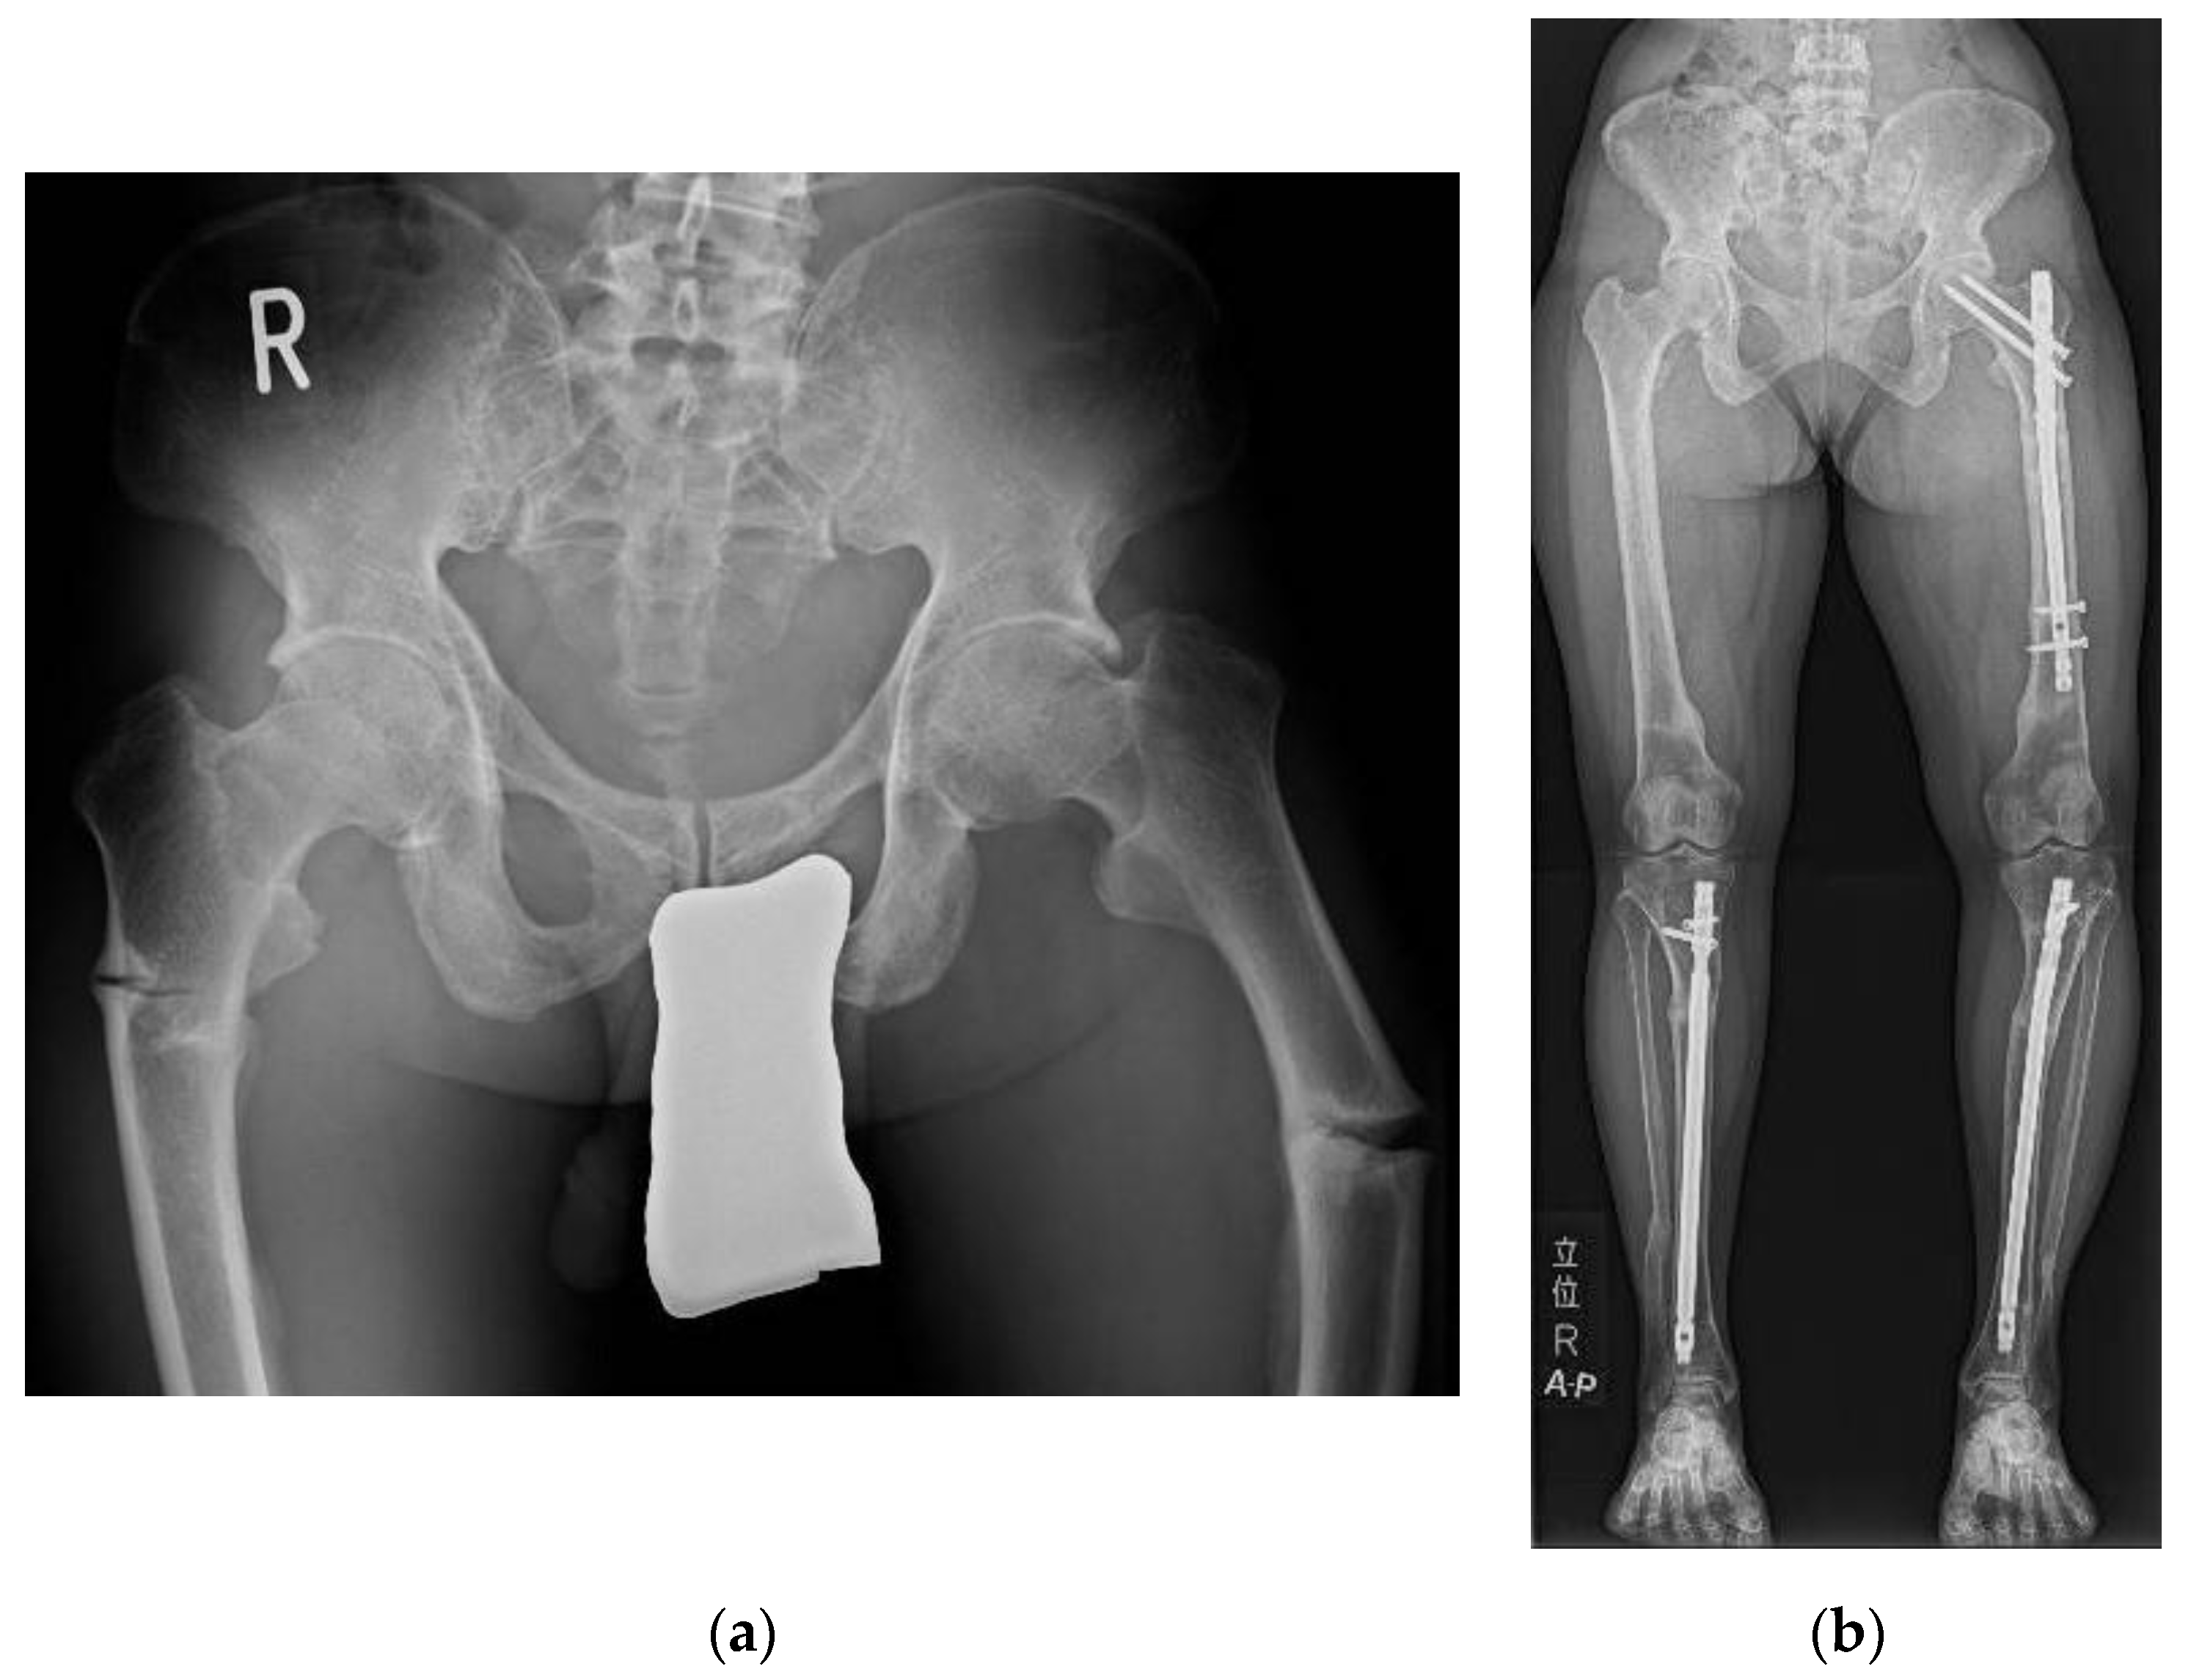

3.1. Pseudofracture and Fracture